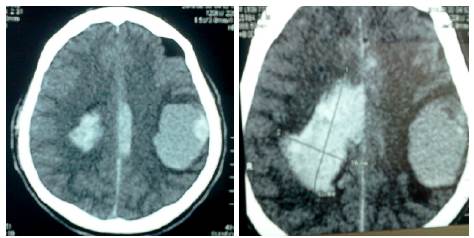

Se realizó TAC sin contraste, en donde se observó una tumoración temporoparietal izquierda, hiperdensa de 4.1x5cm, con edema perilesional y hemorragia que produce efecto expansivo severo, desviación de la línea media e invasión intraventricular (Figura 5).

Tomografía axial computada, lesión metastásica cerebral.

Figura 5: Tomografía axial computada, lesión metastásica cerebral.

Fuente: Documento obtenido durante la realización del estudio.